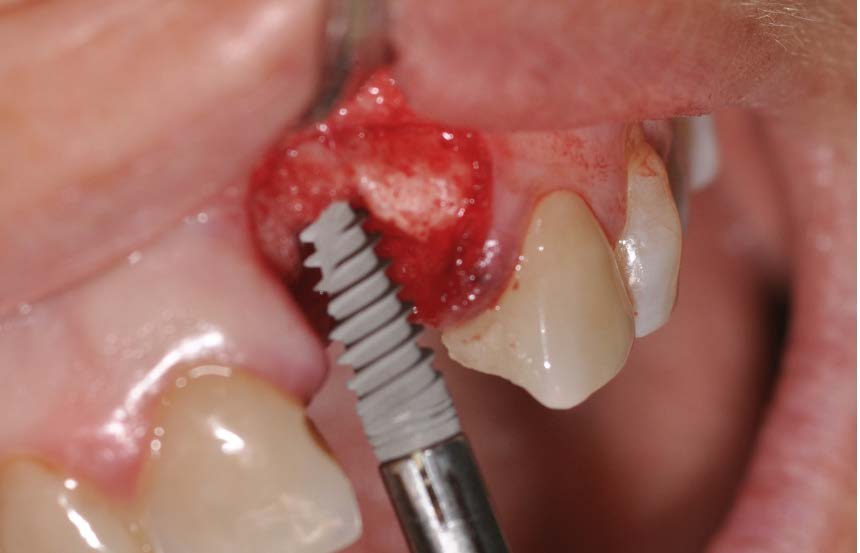

The radiographic examination (intraoral X-ray and Cone Beam Tc scan) shows vertical and horizontal bone defects due to alveolar remodeling following tooth extraction made many years earlier. It was decided to plan an implant insertion surgery and proceed with the insertion of a EV implant with a delayed loading with simultaneous regeneration of hard and soft tissues to obtain the correct volumes for aesthetic success.